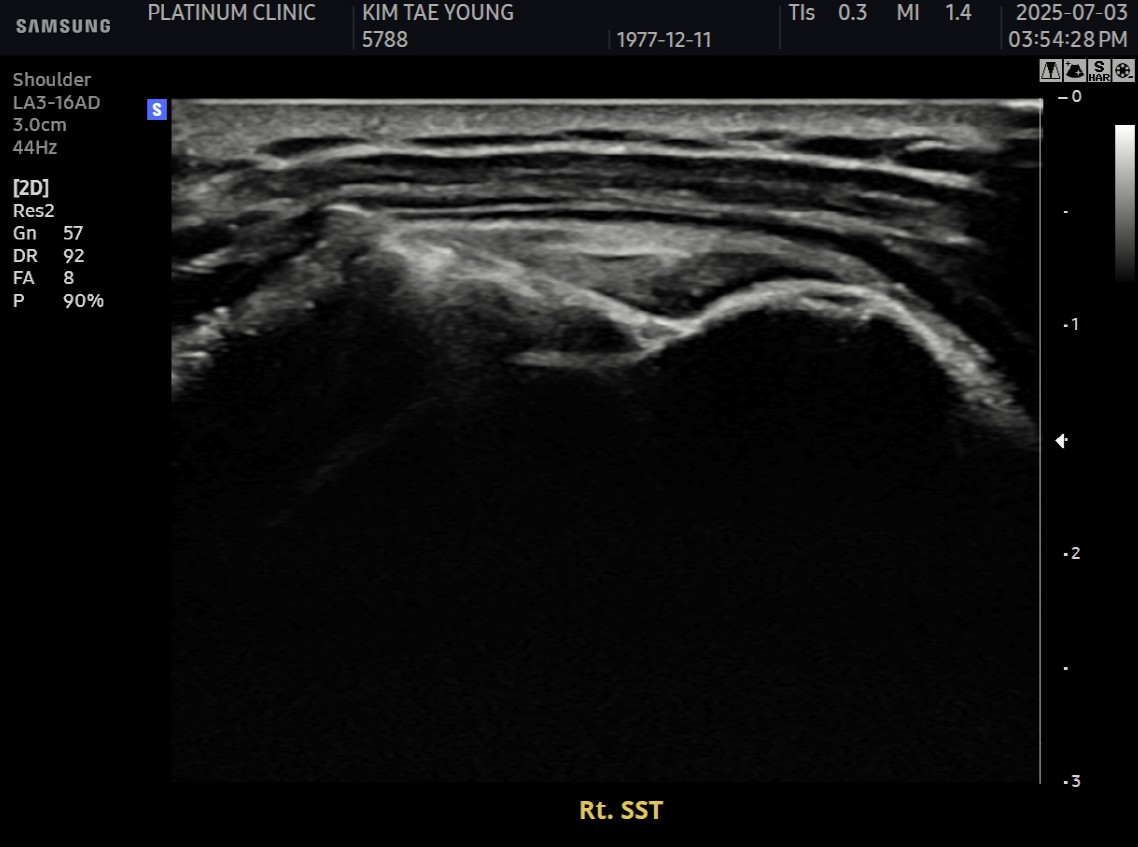

10주 후 초음파:

봉합 부위가 정상 인대처럼 하얗게 재생되어 있었습니다. 골수자극의 효과로 예상보다 빠른 재생이 확인되었습니다.